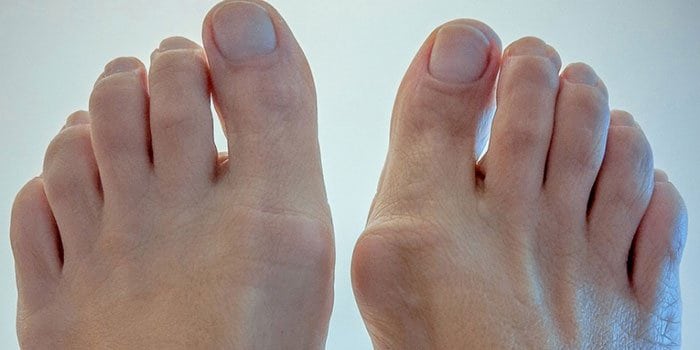

- большой палец искривляется, возникает вальгусная деформация стопы;

Опытной диагност заподозрит развитие плюснефалангового артроза при внешнем осмотре стопы. На патологию указывают развивающаяся вальгусная деформация, отечность большого пальца, подгибание стопы при ходьбе. Для подтверждения диагноза проводятся инструментальные исследования. На рентгенологических снимках заметны сформировавшиеся остеофиты, уменьшение размера суставной щели, обызвествленные участки. При необходимости назначается КТ или МРТ. Эти методы наиболее информативны для обнаружения поражений связок, мышц и сухожилий. Проводятся и лабораторные исследования: